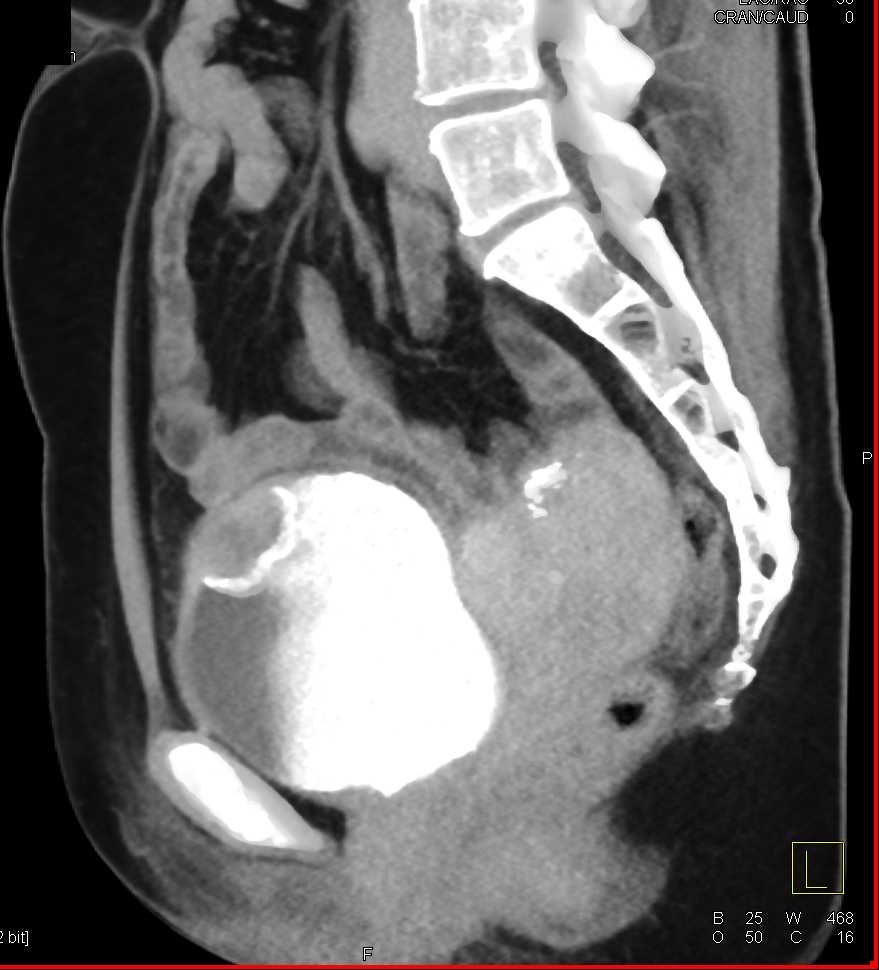

Urachal Carcinoma of the Bladder